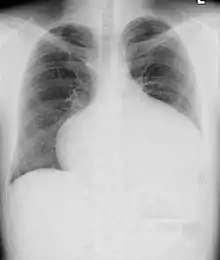

Adults with an uncorrected ASD present with symptoms of dyspnea on exertion (shortness of breath with minimal exercise), congestive heart failure, or cerebrovascular accident (stroke). They may be noted on routine testing to have an abnormal chest X-ray or an abnormal ECG and may have atrial fibrillation. If the ASD causes a left-to-right shunt, the pulmonary vasculature in both lungs may appear dilated on chest X-ray, due to the increase in pulmonary blood flow.[32]

In transthoracic echocardiography, an atrial septal defect may be seen on color flow imaging as a jet of blood from the left atrium to the right atrium.

If agitated saline is injected into a peripheral vein during echocardiography, small air bubbles can be seen on echocardiographic imaging. Bubbles traveling across an ASD may be seen either at rest or during a cough. (Bubbles only flow from right atrium to left atrium if the right atrial pressure is greater than left atrial). Because better visualization of the atria is achieved with transesophageal echocardiography, this test may be performed in individuals with a suspected ASD which is not visualized on transthoracic imaging. Newer techniques to visualize these defects involve intracardiac imaging with special catheters typically placed in the venous system and advanced to the level of the heart. This type of imaging is becoming more common and involves only mild sedation for the patient typically.

If the individual has adequate echocardiographic windows, use of the echocardiogram to measure the cardiac output of the left ventricle and the right ventricle independently is possible. In this way, the shunt fraction can be estimated using echocardiography.